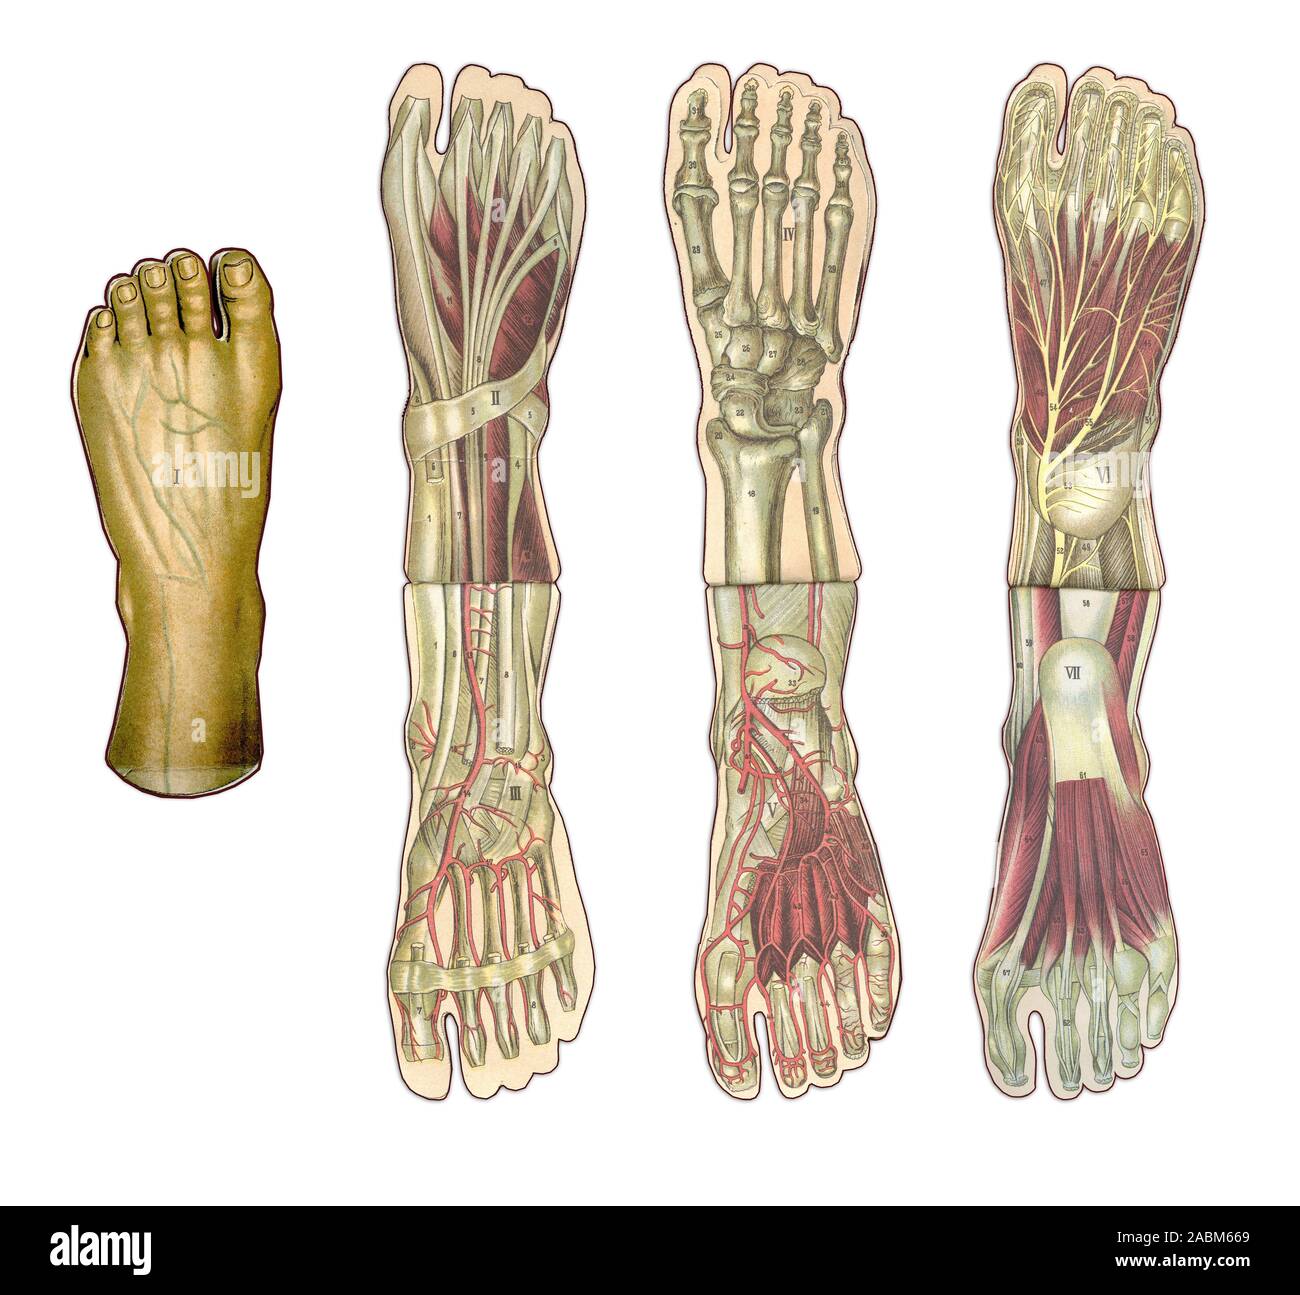

RF2ABM669–La médecine et les soins de l'illustre le tableau, les droits de l'anatomie du pied : Peau et tissus ectodermaux, os, muscles nerfs, vaisseaux sanguins